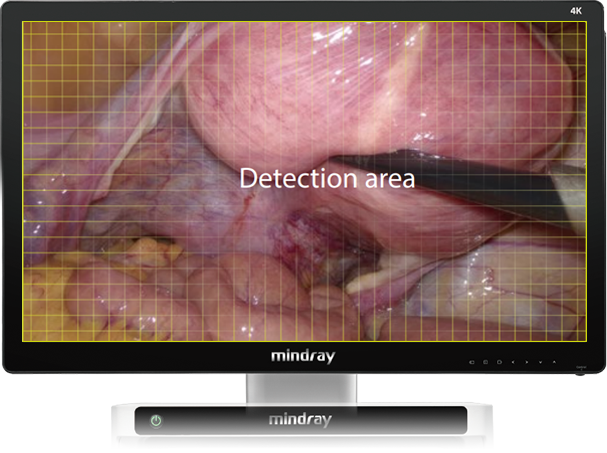

Automatic Scene Recognition, Intelligent Brightness Adjustment

Smart exposure: Determine different detection areas according to different scene and accurately match the exposure parameters without the need to manually switch department modes.

Laparoscope scene